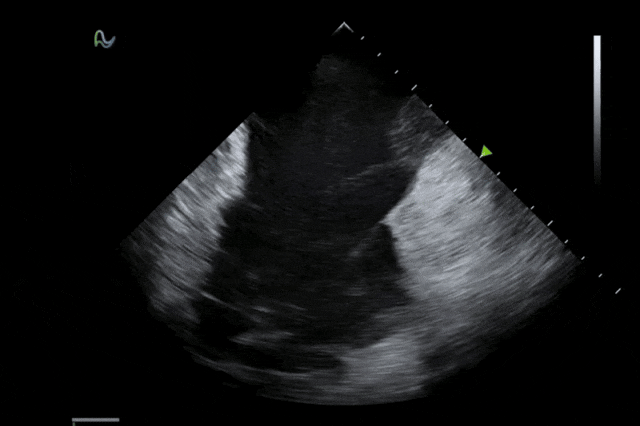

医学成像科学与技术系统全国重点实验室与孵化企业深圳欢影医疗科技有限公司合作研发的"一次性使用心腔内超声诊断导管"正式取得国家药品监督管理局批准上市(三类医疗器械注册证:国械注准20253061587)。作为领域内首款80阵元大孔径高密度探头的心腔内超声导管,其10F/8F双规格设计填补了国内该领域技术空白,为心脏介入手术给予了更精准的国产影像解决方案。

心腔内超声(ICE)被誉为心脏介入手术的"黄金眼",能够顺利获得微创方式实时呈现心脏内部结构和血流成像,为房颤消融、左心耳封堵、先心病介入等手术给予精准成像导航。相较于传统影像手段,ICE具有无辐射、实时成像、操作灵活等显著优势,已成为国际指南推荐的核心诊断技术。

本次获批的ICE导管在全球首次采用了80阵元大孔径高密度探头设计,较传统普通的64阵元产品大幅度提升了成像分辨率、成像深度和图像对比度,可清晰辨识心脏细微结构和血流,为复杂手术给予更可靠的超声成像支持。同时,8F导管凭借更小的外径,显著提升导管顺利获得性和操控性,对病人创伤更小,尤其适合血管条件受限或小心脏患者;10F导管则凭借其优质的成像质量,为复杂心脏介入手术给予精准的影像引导。